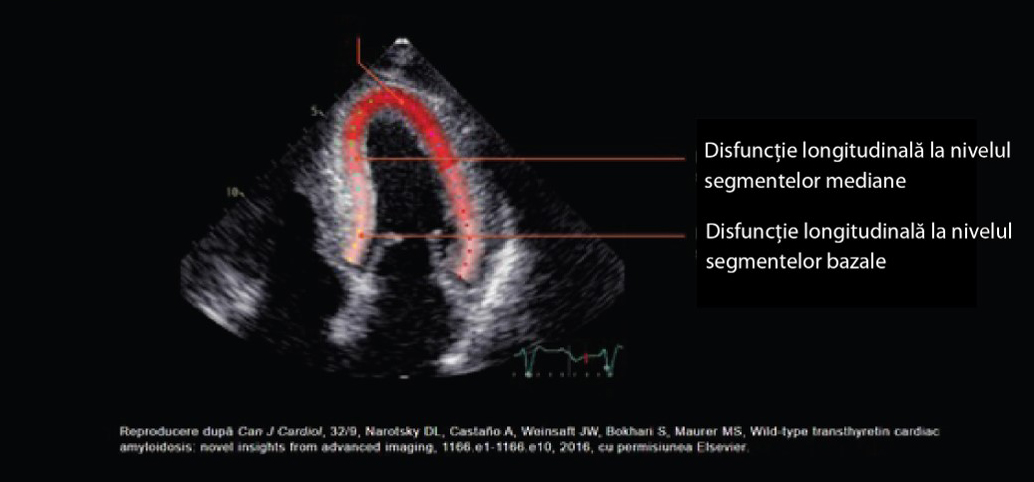

- Indiciile imagistice, precum reducerea strainului longitudinal cu sparing pe segmentul apical, pot creşte suspiciunea clinică1, 9